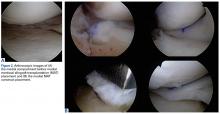

Surgery was started with brief arthroscopic evaluation to confirm the overall appropriateness of the planned procedure and to determine if any other minor deficiencies would warrant operative intervention. Once confirmed, the restoration proceeded as planned. The OWMTO was performed with a PEEK (polyetheretherketone) wedge implant (iBalance; Arthrex) followed by arthroscopic preparation for medial MAT with removal of any meniscal remnants and placement of passing sutures (Figure 2A).

The meniscus was delivered across the compartment through an enlarged medial portal. The posterior horn bone plug was secured in the retrosocket with sutures tied off to an anterior tibial cortical 2-hole button (Figure 2B). The body of the posterior third of the meniscus was secured to the posterior capsule by tying the 2 previously placed vertical sutures to each other over the intervening capsule. The anterior horn bone plug (10 mm in diameter × 7 mm thick) was then secured within a 10-mm socket drilled antegrade to a depth of 10 mm with a SwiveLock anchor (Arthrex) for interference bony fixation and recapitulation of the normal hoop stresses. Inside-out sutures were placed to secure the capsule to the meniscus and thereby prevent iatrogenic meniscal extrusion. A standard all-inside allograft revision ACL reconstruction was performed with an 11-mm FlipCutter and guide system (Arthrex) to make the femoral and tibial retrosockets. Passing sutures were used to deploy the ACL graft construct, which was fashioned into a quadruple-stranded GraftLink construct (Arthrex) from a 28-mm allograft peroneus longus tendon (Figure 3).When the arthroscopic portion of the surgery was finished, a medial parapatellar arthrotomy was made to allow the patella to be inverted and complete fresh mega-patellar OCA placement (Figure 4).